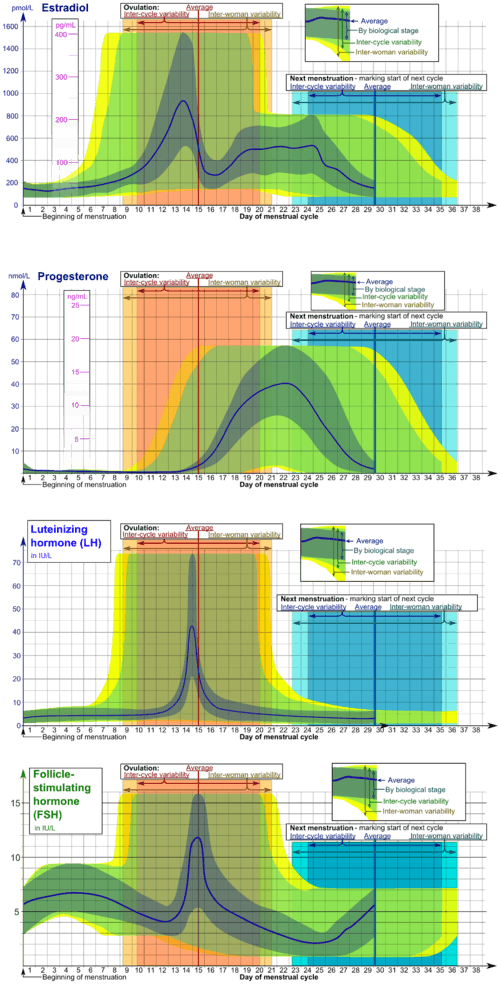

The menstrual cycle is governed by hormonal changes.[6] These changes can be altered by using hormonal birth control to prevent pregnancy.[9] Each cycle can be divided into three phases based on events in the ovary (ovarian cycle) or in the uterus (uterine cycle).[1] The ovarian cycle consists of the follicular phase, ovulation, and luteal phase whereas the uterine cycle is divided into menstruation, proliferative phase, and secretory phase.

Stimulated by gradually increasing amounts of estrogen in the follicular phase, discharges of blood (menses) flow stop, and the lining of the uterus thickens. Follicles in the ovary begin developing under the influence of a complex interplay of hormones, and after several days one or occasionally two become dominant (non-dominant follicles shrink and die). Approximately mid-cycle, 24–36 hours after the luteinizing hormone (LH) surges, the dominant follicle releases an ovocyte, in an event called ovulation. After ovulation, the ovocyte only lives for 24 hours or less without fertilization while the remains of the dominant follicle in the ovary become a corpus luteum; this body has a primary function of producing large amounts of progesterone. Under the influence of progesterone, the uterine lining changes to prepare for potential implantation of an embryo to establish a pregnancy. If implantation does not occur within approximately two weeks, the corpus luteum will involute, causing a sharp drop in levels of both progesterone and estrogen. The hormone drop causes the uterus to shed its lining in a process termed menstruation. Menstruation also occurs in some other animals including shrews, bats, and other primates such as apes and monkeys.[10]

Through the influence of a rise in follicle stimulating hormone (FSH) during the first days of the cycle, a few ovarian follicles are stimulated.[63] These follicles, which were present at birth[63] and have been developing for the better part of a year in a process known as folliculogenesis, compete with each other for dominance. Under the influence of several hormones, all but one of these follicles will stop growing, while one dominant follicle in the ovary will continue to maturity. The follicle that reaches maturity is called a tertiary, or Graafian, follicle, and it contains the ovum.[63]

Ovulation

Ovulation is the second phase of the ovarian cycle in which a mature egg is released from the ovarian follicles into the oviduct.[64] During the follicular phase, estradiol suppresses production of luteinizing hormone (LH) from the anterior pituitary gland. When the egg has nearly matured, levels of estradiol reach a threshold above which this effect is reversed and estrogen stimulates the production of a large amount of LH. This process, known as the LH surge, starts around day 12 of the average cycle and may last 48 hours.[65]

The exact mechanism of these opposite responses of LH levels to estradiol is not well understood.[66] In animals, a gonadotropin-releasing hormone (GnRH) surge has been shown to precede the LH surge, suggesting that estrogen's main effect is on the hypothalamus, which controls GnRH secretion.[66] This may be enabled by the presence of two different estrogen receptors in the hypothalamus: estrogen receptor alpha, which is responsible for the negative feedback estradiol-LH loop, and estrogen receptor beta, which is responsible for the positive estradiol-LH relationship.[67] However, in humans it has been shown that high levels of estradiol can provoke abrupt increases in LH, even when GnRH levels and pulse frequencies are held constant,[66] suggesting that estrogen acts directly on the pituitary to provoke the LH surge.

Luteal phase

The luteal phase is the final phase of the ovarian cycle and it corresponds to the secretory phase of the uterine cycle. During the luteal phase, the pituitary hormones FSH and LH cause the remaining parts of the dominant follicle to transform into the corpus luteum, which produces progesterone. The increased progesterone in the adrenals starts to induce the production of estrogen. The hormones produced by the corpus luteum also suppress production of the FSH and LH that the corpus luteum needs to maintain itself. Consequently, the level of FSH and LH fall quickly over time, and the corpus luteum subsequently atrophies.[63] Falling levels of progesterone trigger menstruation and the beginning of the next cycle. From the time of ovulation until progesterone withdrawal has caused menstruation to begin, the process typically takes about two weeks, with 14 days considered normal. For an individual woman, the follicular phase often varies in length from cycle to cycle; by contrast, the length of her luteal phase will be fairly consistent from cycle to cycle.[73]

Proliferative phase

The proliferative phase is the second phase of the uterine cycle when estrogen causes the lining of the uterus to grow, or proliferate, during this time.[63] As they mature, the ovarian follicles secrete increasing amounts of estradiol, and estrogen. The estrogens initiate the formation of a new layer of endometrium in the uterus, histologically identified as the proliferative endometrium. The estrogen also stimulates crypts in the cervix to produce fertile cervical mucus, which may be noticed by women practicing fertility awareness.[83]

Secretory phase

The secretory phase is the final phase of the uterine cycle and it corresponds to the luteal phase of the ovarian cycle. During the secretory phase, the corpus luteum produces progesterone, which plays a vital role in making the endometrium receptive to implantation of the blastocyst and supportive of the early pregnancy, by increasing blood flow and uterine secretions and reducing the contractility of the smooth muscle in the uterus;[84] it also has the side effect of raising the woman's basal body temperature.[85]